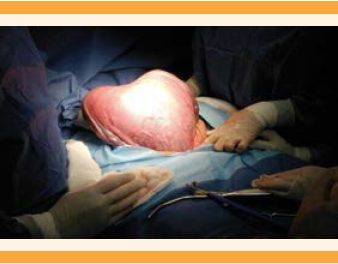

Durante las primeras 48 horas tuvo sangrado transvaginal profuso (mayor de 200 mL, de color rojo rutilante, no doloroso); no se registraron datos de gasto cardiaco, pero se observó pérdida del bienestar fetal (bradicardia de 100 lpm mediante registro electrocardiotocográfico), por lo que se decidió la interrupción del embarazo por cesárea de urgencia. Puesto que se trataba de un embarazo con alta morbilidad y mortalidad, y la paciente tenía paridad satisfecha, se decidió realizar cesárea-histerectomía con la técnica de Esperanza-Bautista (Figura 3). Se obtuvo un recién nacido femenino, con peso de 1416 g, Capurro de 3 semanas y APGAR 7/9. Los hallazgos más sobresalientes fueron: placenta previa total, con proliferación anormal del trofoblasto, vesículas y edema velloso (Figura 4). No se registraron incidentes ni complicaciones pre ni posoperatorias. Se estimó un sangrado de 700 mL. Durante el seguimiento, 72 horas después de la cesárea, la concentración de la fracción β-hCG fue de 16,549 mUI/mL y después de una semana de 3,984 mUI/mL. Por el momento la paciente permanece en seguimiento semanal; cuando cumpla tres semanas consecutivas con resultado negativo continuará la determinación de β-hCG cada dos semanas por dos meses y, finalmente, de manera mensual durante un año. El reporte de patología fue proliferación anormal del trofoblasto, vesículas y vellosidades hidrópicas (Figura 5).